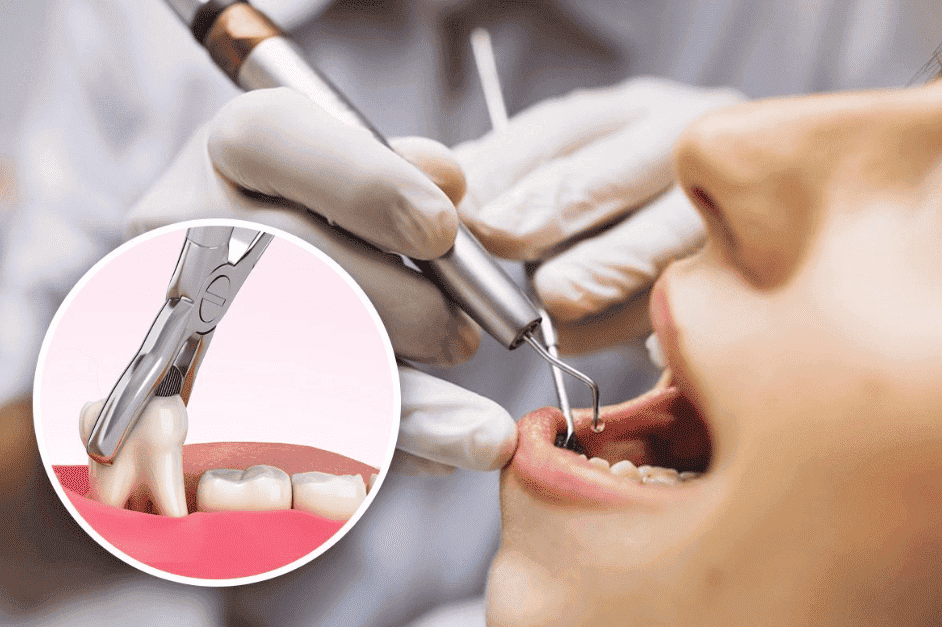

Tooth Extraction

Tooth extraction involves the removal of a tooth from its socket in the jawbone and gum tissue. This procedure is performed to address various dental issues such as severe decay, periodontal disease, impacted wisdom teeth, overcrowding, or preparation for orthodontic treatment. By removing problematic teeth, patients can experience relief from pain, prevent further dental problems, and improve overall oral health.

Tooth Extraction Treatment involves several steps:

- Evaluation: Our dental team assesses the condition of the tooth and surrounding tissues to determine the best approach for extraction.

- Anesthesia: Local anesthetics are administered to numb the area and ensure a comfortable experience during the procedure.

- Extraction: Using specialized tools such as dental forceps and elevators, the tooth is gently removed from its socket.

- Aftercare: Post-extraction instructions are provided to promote healing and prevent complications.